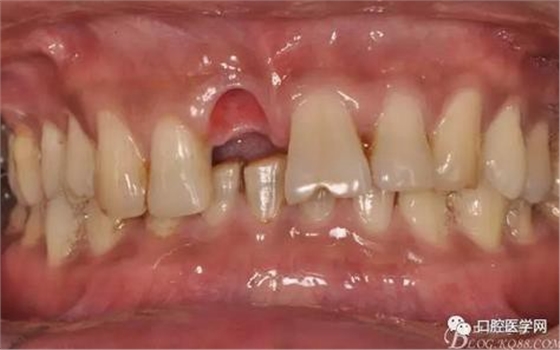

圖9 三個月后袖口形成正位照